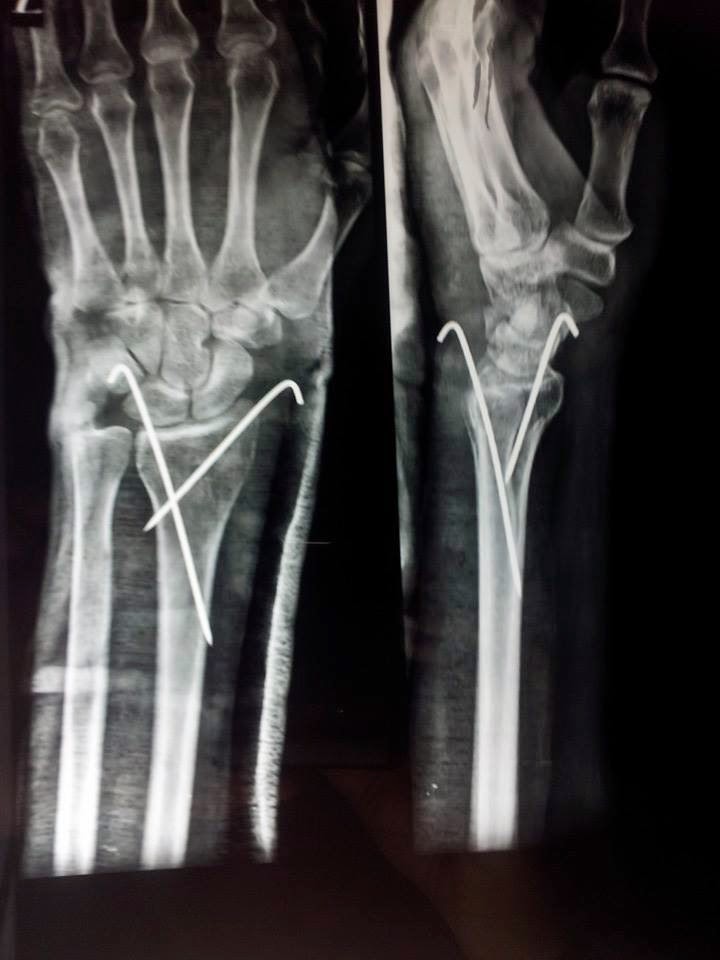

In this era of universal plating, I still prefer K-wires for simple distal radius metaphyseal fractures, particularly in young patients (low risk of stiffness) and non-dominant extremity (less interference with ADL).

Bansal Ajay With such a degree of dorsal angulation, implying collapse of dorsal cortex, its better to supplement the cast with K-wire fixation, to prevent recollapse. -

Sudhir Pai 5-wire fixation also is an easy practical technique that allows early mobilisation (except rotation) & no chance of sub-chondral collapse.

Anuj Agrawal Sudhir Pai DRUJ pinning, if required, should be done just proximal to the joint, rather than through it, as taught by Srinivas Daravathu.